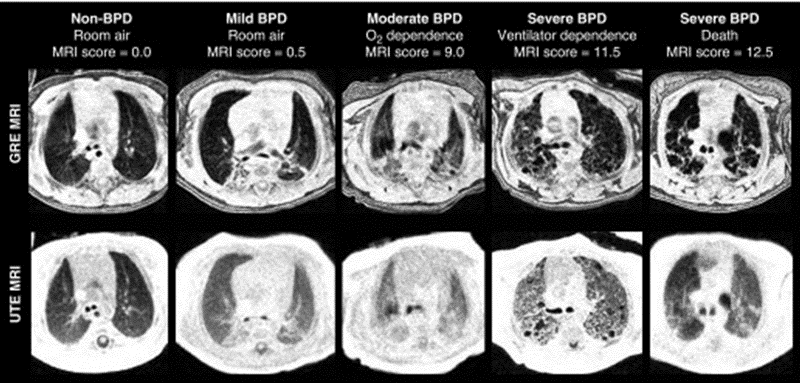

Imaging of Regional Lung Ventilation in Infants

We aim to create novel imaging-based phenotyping of lung ventilation abnormalities in neonatal lung disease by employing pulmonary MRI with proton-density weighting and self-navigated gating, thus providing dynamic quantification of the 3D structure during free-breathing. Neonatal diseases of interest include bronchopulmonary dysplasia (BPD, otherwise known as chronic lung disease of prematurity) and pulmonary hypoplasia (underdeveloped lung tissue, frequently seen in congenital disorders such as congenital diaphragmatic hernia, CDH). The underlying lung abnormalities, their relationship to outcomes, and response to clinical care management is often poorly understood in patients with these conditions.